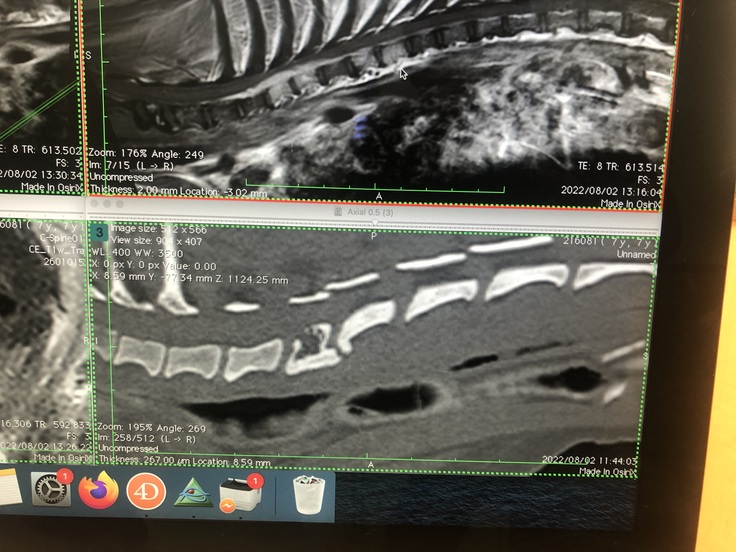

※腫瘍部を拡大して画像になります、縦に白い柱が、腫瘍に侵されてしまった骨です

左側、白い骨の上部に細長い雲の様に見える物も腫瘍です。

赤丸の中、縦に白くなっている部位が、腫瘍に侵された骨です、

左側2本の白い部位の上に細長い白い雲のような物も腫瘍になります。

赤丸、左側が、1年4ヶ月前に発症した、最初の病巣になります、

約3センチ下に、今回の病巣になります。この腫瘍が、後ろ足の麻痺、排尿困難を引き起こして

います。同時に痛みも。

※検査画像 下段の真ん中付近 穴の開いた骨が確認できます。

頚椎6番になります。この骨の8/2日 現在の状態です、

奇跡的に温存出来ています。